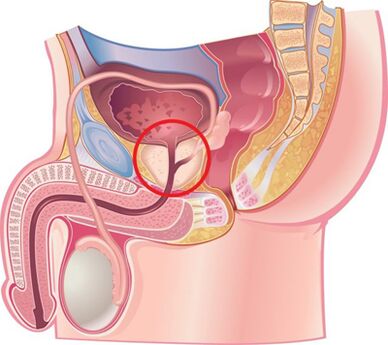

Palpation der Prostata

Von vorrangiger Bedeutung für die Diagnose der Krankheit ist das Abtasten der Prostata, das während der Exazerbationsphase zunimmt und während der Abschwächung des Entzündungsprozesses abnimmt. Bei chronischer Prostatitis schwillt die Drüse während der Exazerbationsphase an und schmerzt.

Die Konsistenz des Organs kann unterschiedlich sein: Erweichungs- und Verhärtungsbereiche werden abgetastet, Retraktionsbereiche bestimmt. Durch Abtasten ist es möglich, die Form der Drüse, den Zustand der Samenhöcker und des umgebenden Gewebes zu beurteilen.

Der Prozess der transrektalen digitalen Untersuchung wird mit der Sammlung von Drüsensekreten kombiniert. Manchmal ist es notwendig, das Sekret aus jedem Lappen separat zu entnehmen.